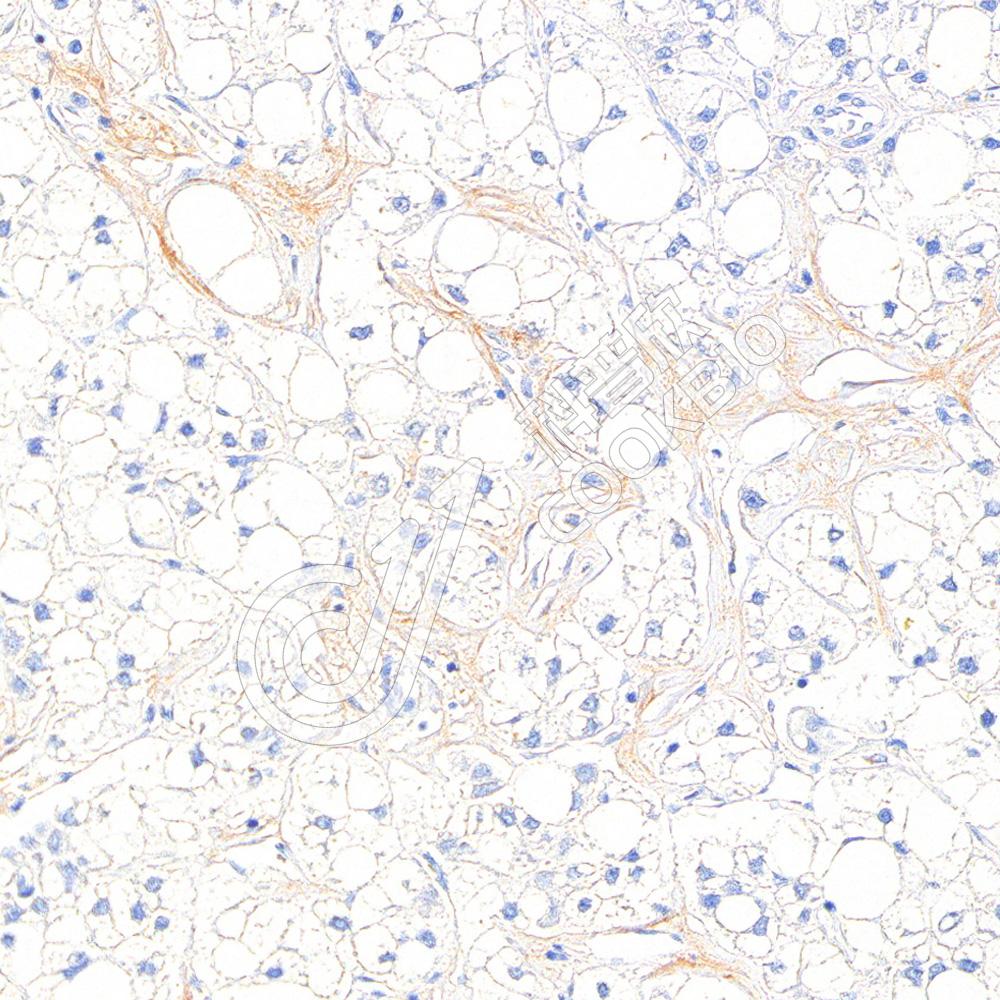

IHC检测Collagen III蛋白(货号 K2364887).

样品: 人肾, 4%多聚甲醛 (货号KSG1101) 固定12-24小时.

抗原修复: 柠檬酸抗原修复液(干粉, pH 6.0) (KSG1201), 高压锅均匀喷气计时2分钟.

—抗: 1: 1000稀释, 4℃ 孵育过夜.

二抗: S-vision免疫组化多聚二抗(山羊抗小鼠), 即用型(货号KB3903), 室温孵育20分钟.

样品: 人肝癌, 4%多聚甲醛 (货号KSG1101) 固定12-24小时.